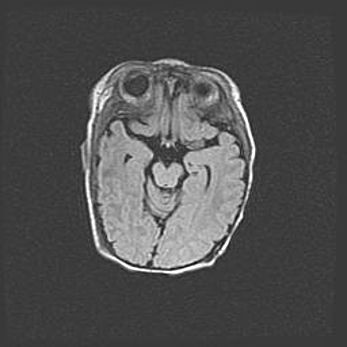

Множественные кисты обоих полушарий головного мозга, наибольшая из них в правой затылочной области. Ассиметричная атрофическая гидроцефалия.

Возраст: 7 месяцев

Вес: 5660 г

Пол: мужской

Окружность головы: 41,5 см

Срок гестации: 28-29 недель

Кисты головного мозга развиваются в результате многоочаговых некрозов вещества мозга и возникают вследствие перенесенной перинатальной инфекции, менингитов, энцефалитов, асфиксии, родовой травмы, расстройств мозгового кровообращения различного генеза. Образованию кист в веществе головного мозга плодов и новорожденных способствуют такие факторы, как высокое содержание в нем воды, недостаточная (или отсутствие) миелинизация и слабая астроглиальная реакция на повреждение.

Кисты могут сочетаться с гидроцефалией и другими поражениями головного мозга.